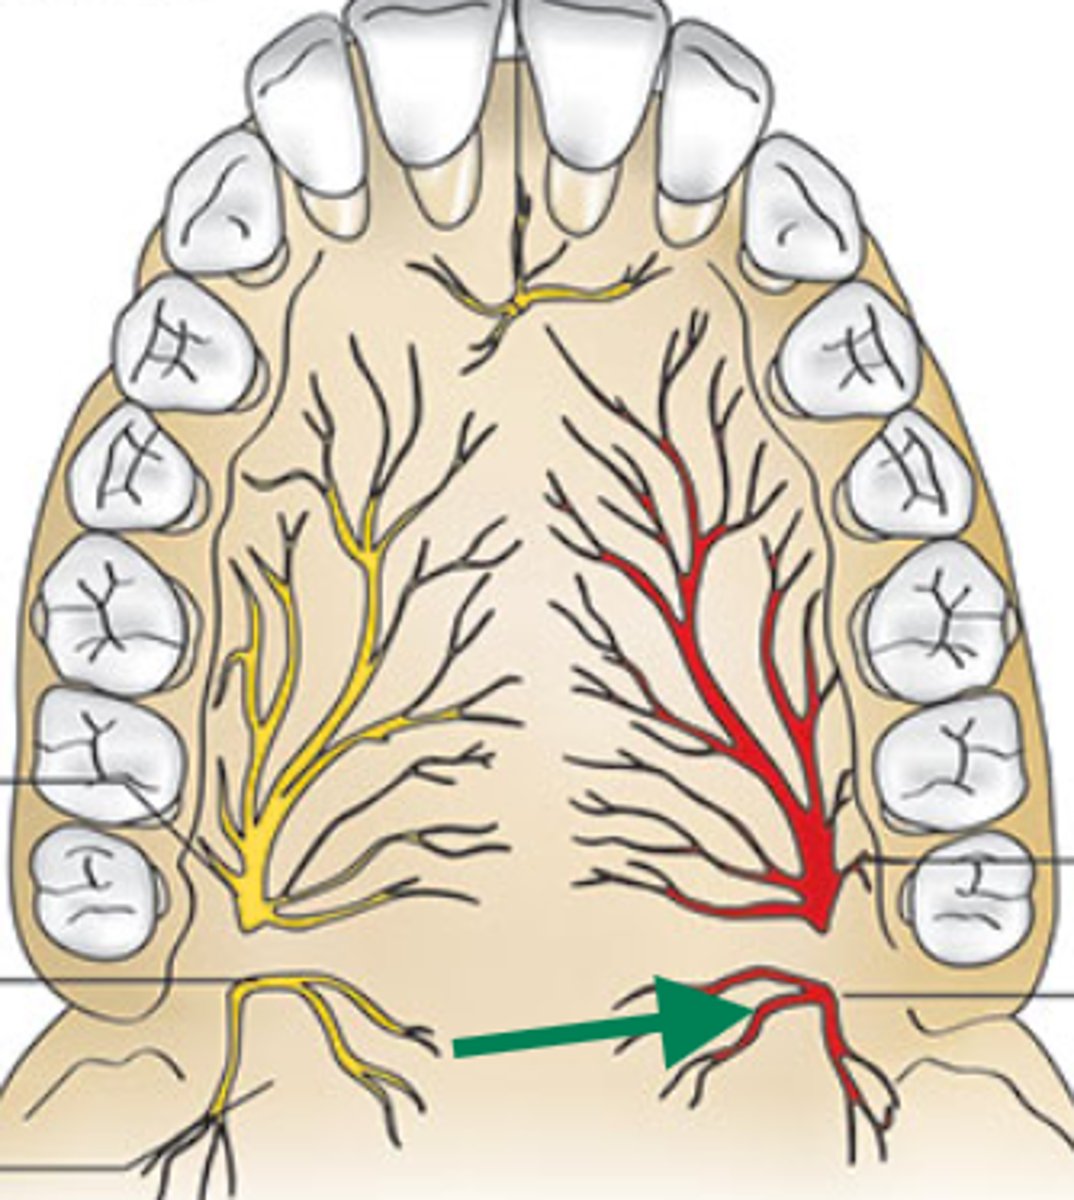

nasopalatine nerve

descending palatine artery

greater palatine nerve

greater palatine artery

greater palatine foramen

lesser palatine nerve

lesser palatine artery

greater and lesser palatine nerve

greater palatine nerve